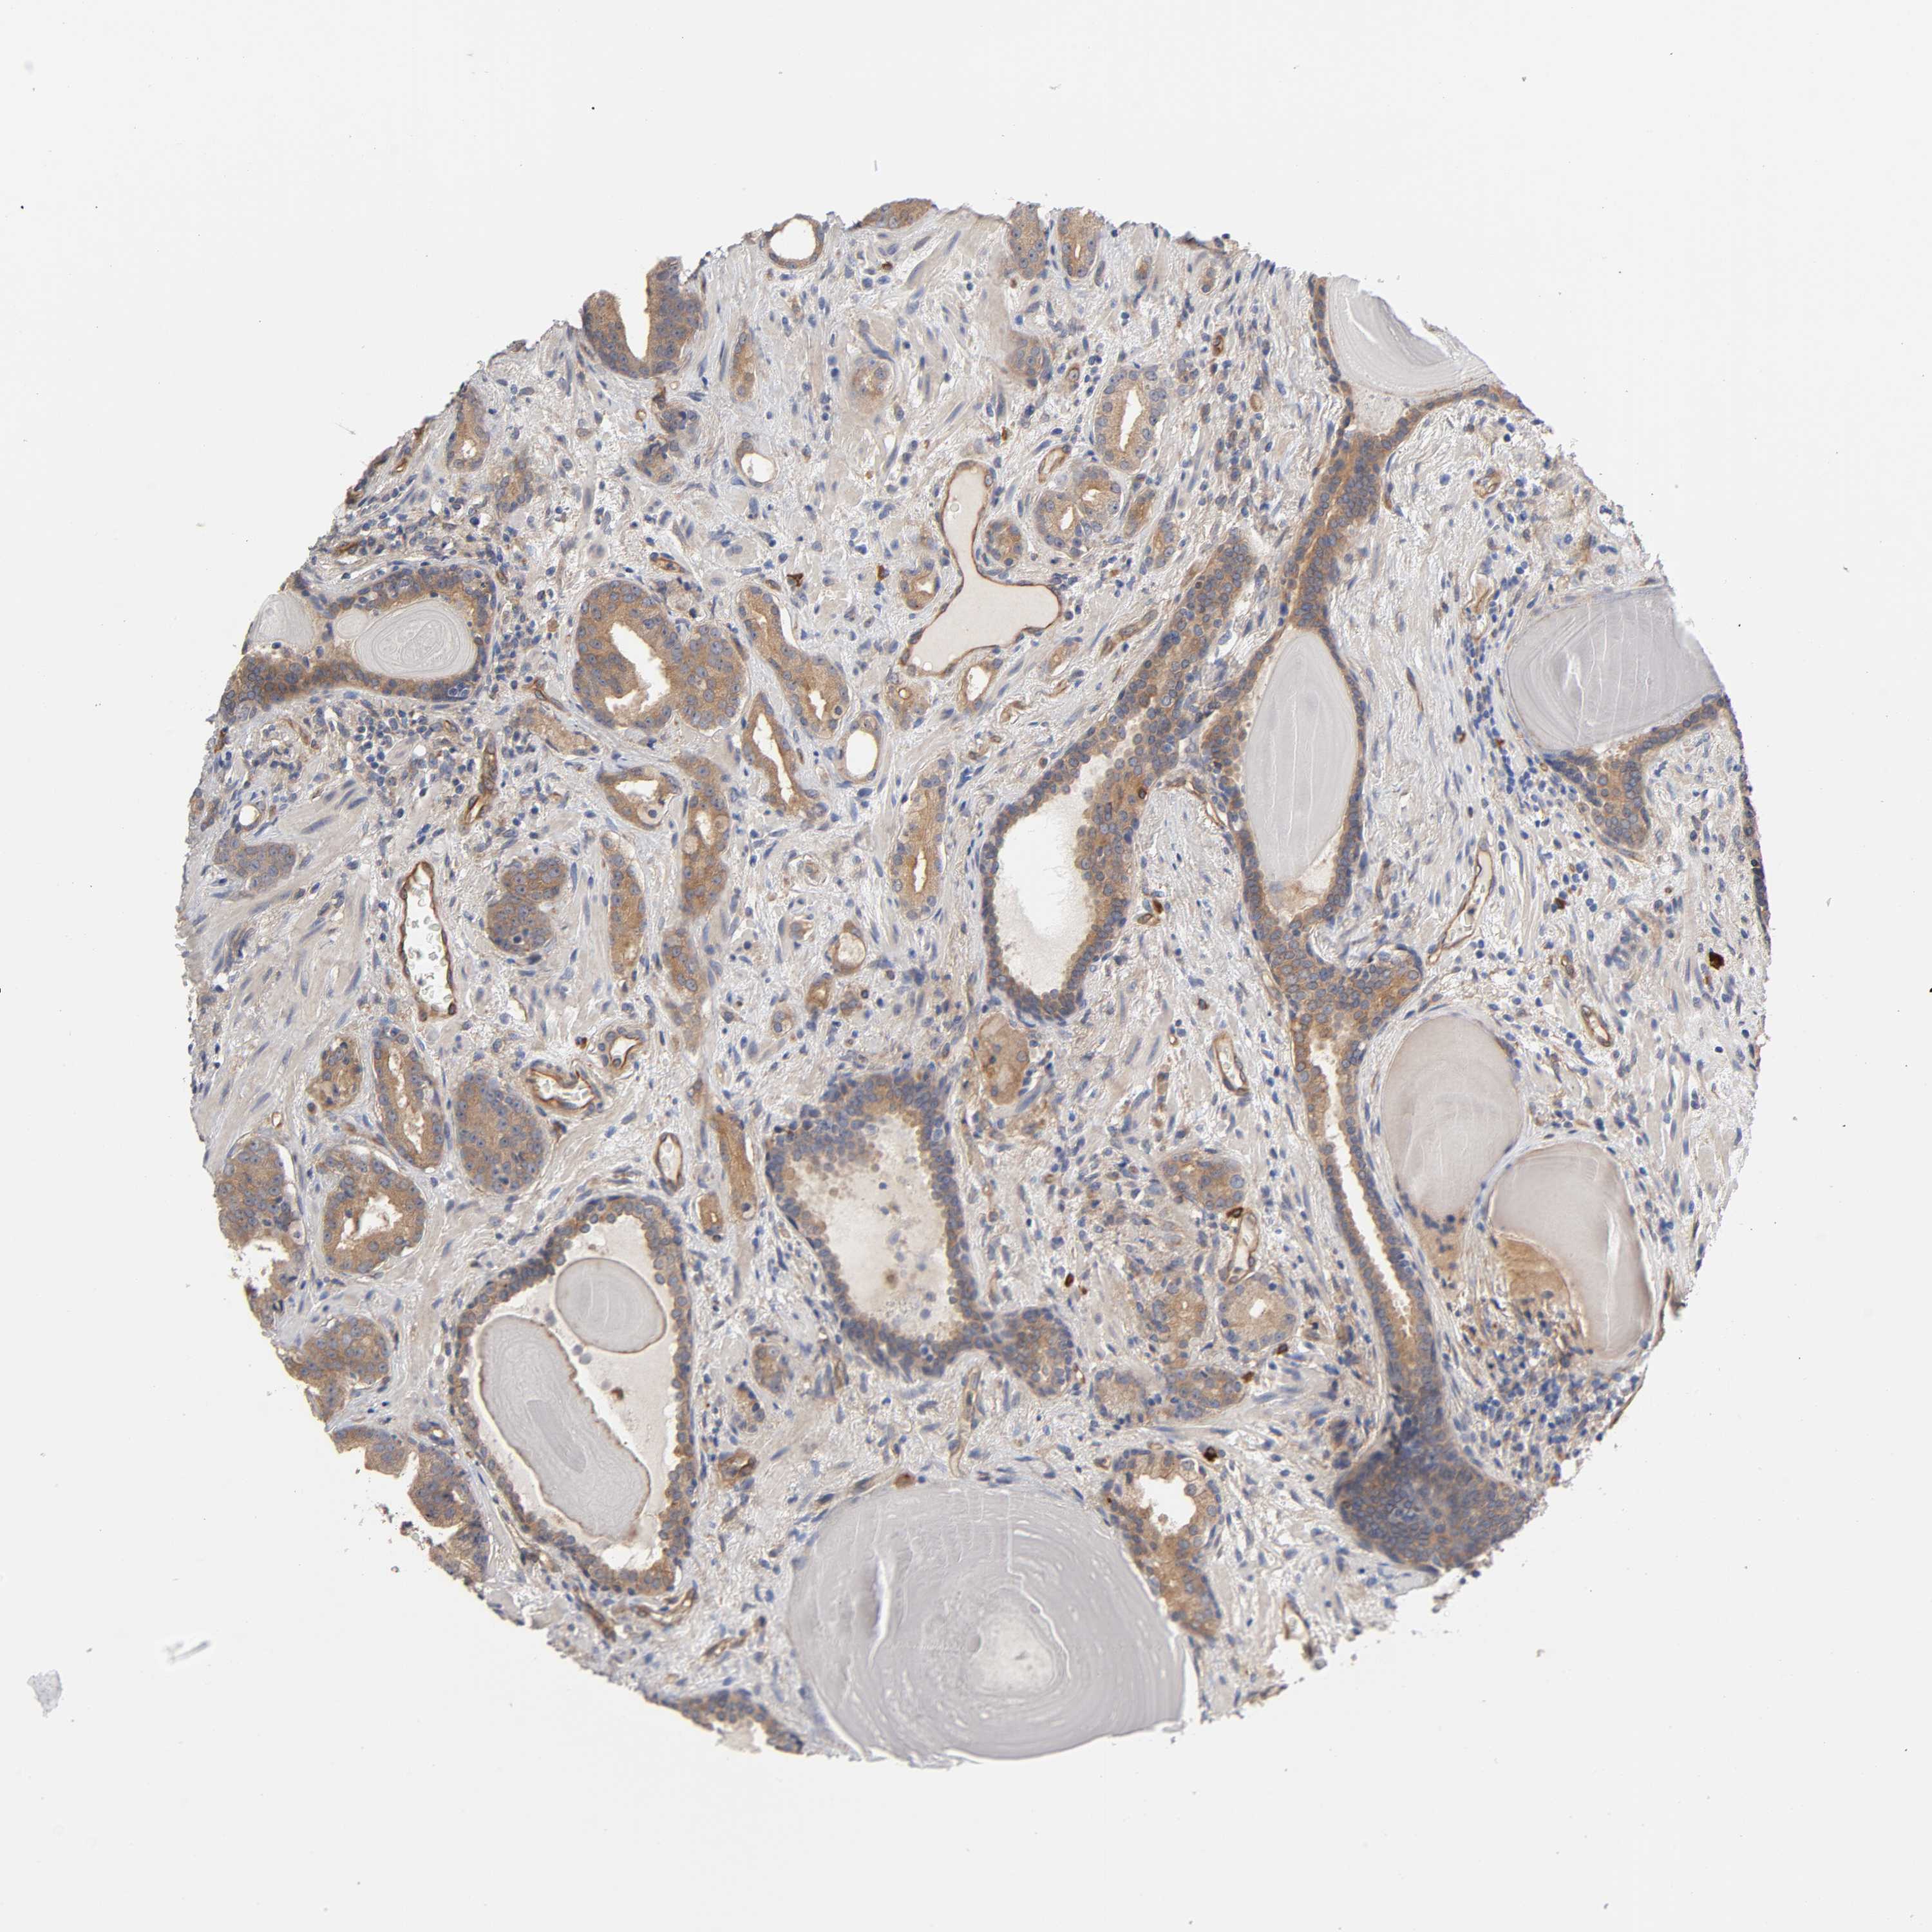

PROSTATE CANCER - Protein expressioni

A mouse-over function shows sample information and annotation data. Click on an image to view it in a full screen mode. Samples can be filtered based on level of antibody staining by selecting one or several of the following categories: high, medium, low and not detected. The assay and annotation is described here.

Note that samples used for immunohistochemistry by the Human Protein Atlas do not correspond to samples in the TCGA dataset.

Antibody stainingi

Antibody staining in the annotated cell types in the current human tissue is reported as not detected, low, medium, or high, based on conventional immunohistochemistry profiling in selected tissues. This score is based on the combination of the staining intensity and fraction of stained cells.

Each image is clickable and will lead to virtual microscopy that enables deeper exploration of all samples and also displays staining intensity scores, fraction scores and subcellular localization as well as patient and tissue information for each sample.

Antibody HPA003996

Staining

High

Medium

Low

Not detected

Intensity

Strong

Moderate

Weak

Negative

Quantity

>75%

75%-25%

<25%

None

Location

Nuclear

Cytoplasmic/membranous

Cytoplasmic/membranous,nuclear

Adenocarcinoma, Low grade

Adenocarcinoma, High grade